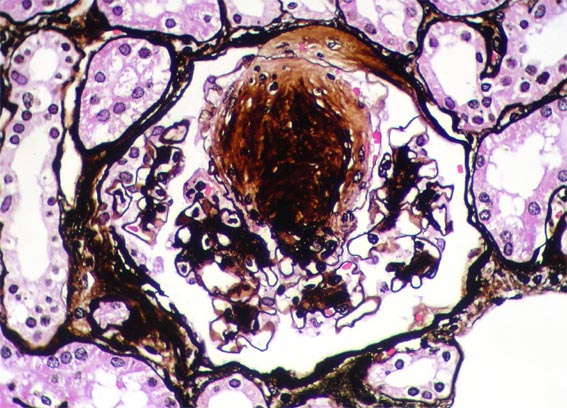

Figura 7.

Plata-metenamina, X400.

3 glomérulos con estos nódulos grandes. Plata-metenamina,

X400.